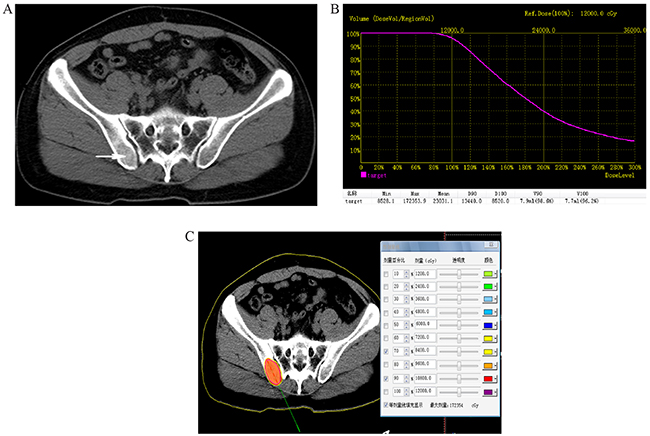

Before 125I brachytherapy, 5mm axial enhanced CT images were obtained in all patients (Figure 1A). Treatment was mapped and dosed for each patient using a computerized treatment planning system (TPS) (RT-RSI, Beijing Atom and High Technique Industries Inc, Beijing, China).

Figure 1: A. Preoperative computed tomography (CT) image was obtained for targeting bone areas of interest, which showed one lesion in right iliac bone (arrowhead). B. Dose volume histograms (DVH). The prescription dose is 120 Gy during the planning. A total of 90% of the tumor target (D90) received 134.4 Gy, and 96.2% of the tumor received 100% of the prescribed dose (V100 = 96.2%). C. Isodose curves plotted by the treatment planning system (TPS), the planning target volume (PTV) edge was covered by isodose curve from 70% to 90%.

A careful delineation of the gross tumor volume (GTV), planned target volume (PTV) and surrounding vital organs (e.g. spinal cord) was sought in every CT slice. PTV is defined as a 1.5 cm of expansion external to the GTV. The prescribed dose was averaged 120 Gy (range 100-140 Gy). Based on three orthogonal diameters within the target tumor and a prescribed matched peripheral dose (MPD) of averaging 120 Gy, TPS generated a dose-volume histogram (DVH), isodose curves of different percentages, and calculated the position of brachytherapy applicator, dose and number of implanted seeds (Figure 1B, 1C). The PTV edge was accounted by the 70%-90% isodose curve. The entry site and path of the needle were determined to avoid vital organs and tissues.